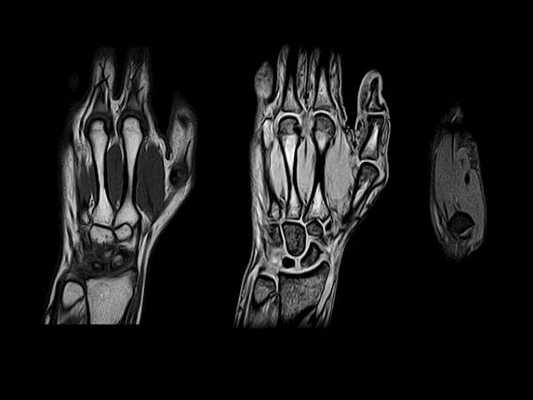

3. МРТ при сесамовидных костях запястья и кисти:

• Нормальные мелкие и сесамовидные кости: интактный кортикальный слой, нормальный сигнал костного мозга без отека кости или мягких тканей

о МРТ: используют специальное кольцо для запястья